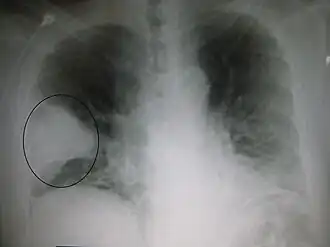

Le diagnostic repose sur :

- la radiographie du thorax, de face et de profil ou l’échographie pulmonaire[8]

Une radiographie du thorax de face est à réaliser systématiquement[10] sauf chez les enfants ou les femmes enceintes où l’usage de l'échographie pulmonaire est aussi efficace avec un opérateur entrainé tout en exposant pas le patient aux rayonnements ionisants[9].

En cas de difficulté diagnostique, un scanner thoracique avec ou sans injection peut être réalisé. En cas de doute diagnostique avec une embolie pulmonaire, l'angioscanner thoracique permet d'éliminer cette dernière.